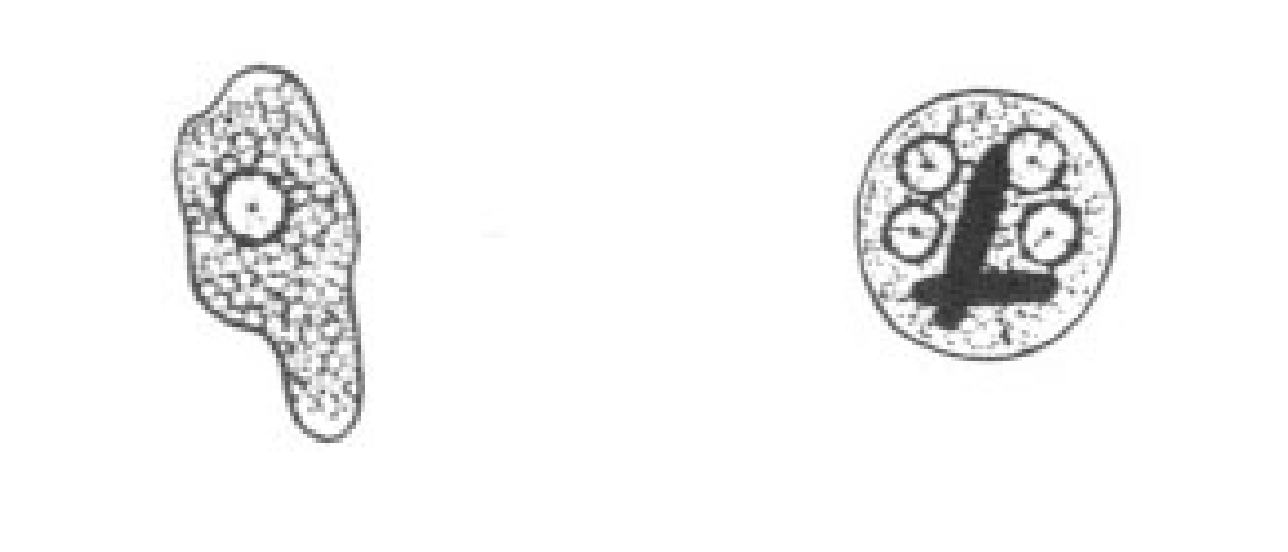

Entamoeba histolytica troph

Entamoeba histolytica troph

Chromatoid bodies have rounded or blunt ends in the Cyst form of this parasite and it is pathogenic

Entamoeba histolytica

Entamoeba histolytica cyst